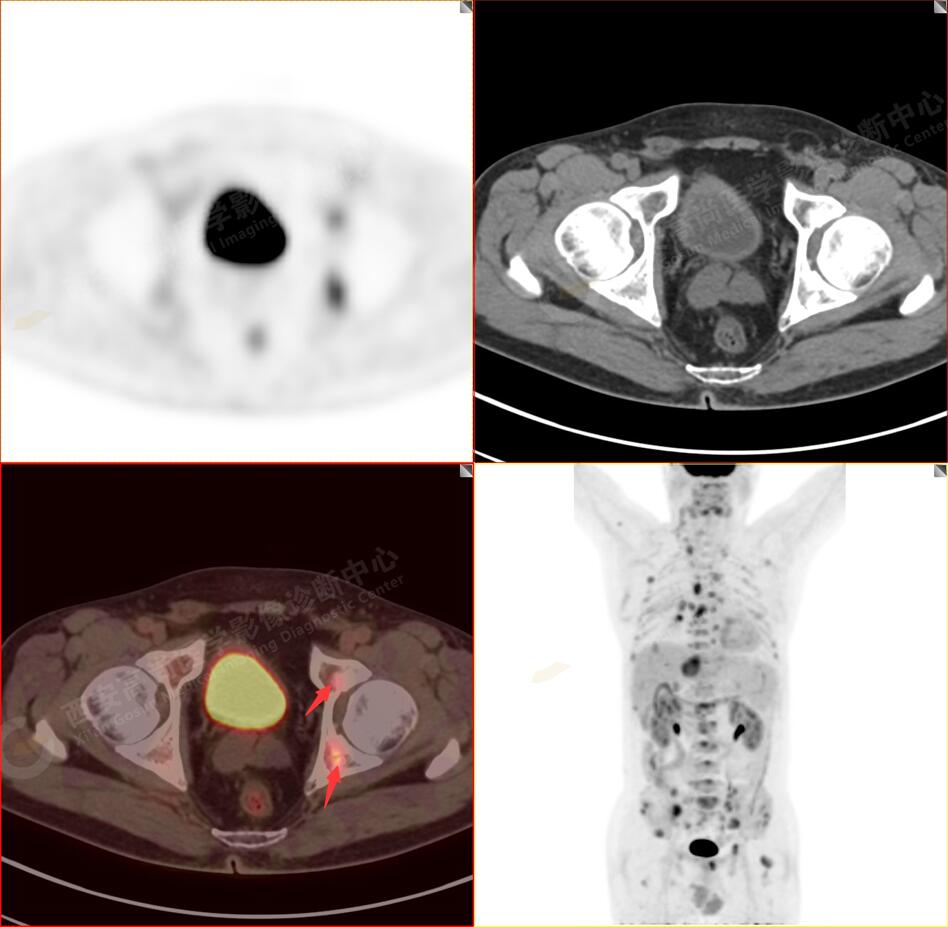

2.以下為全身多發(fā)轉移灶

5.右側肱骨上段、左側肩胛骨、右側鎖骨胸骨端、胸骨、雙側多發(fā)肋骨、脊柱多發(fā)椎體及附件、雙側髂骨、雙側髖臼、雙側恥骨、雙側肱骨上段多發(fā)成骨性病變,呈不同程度FDG代謝異常增高,考慮為多發(fā)骨轉移瘤。